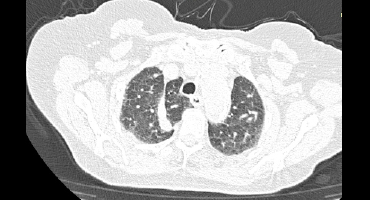

Tomografía

CISURA ACCESORIA DE LA VENA ACIGOS